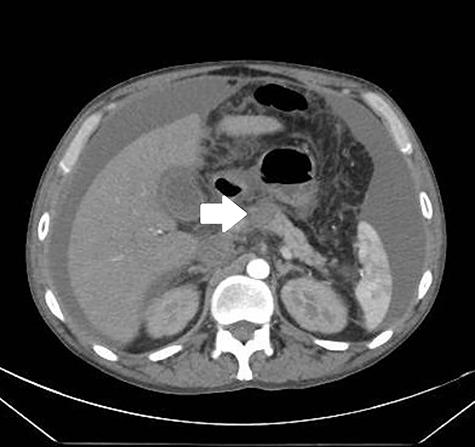

腹部CT显示胰腺坏死伴萎缩(图1,箭头)。